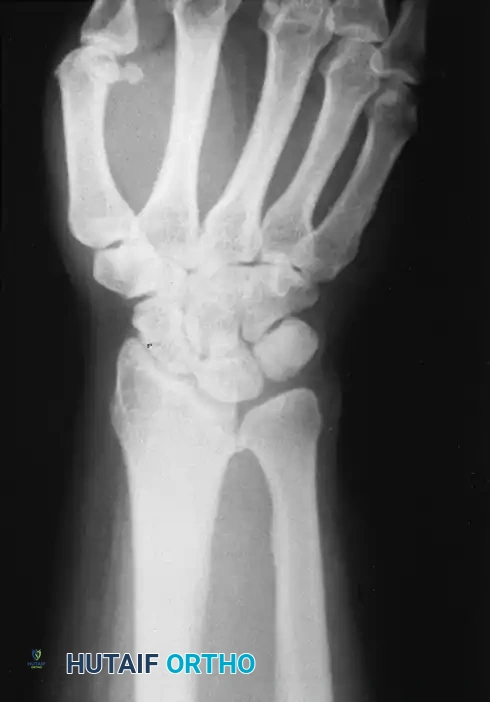

يعتبر التصوير بالأشعة السينية القياسية من الزوايا الأمامية والجانبية أمرا حتميا ولا غنى عنه. من خلال هذه الصور، يقوم الطبيب بقياس زوايا ميل العظام، وتحديد مدى انزلاق عظام الرسغ، ومقارنة طول عظمة الزند بعظمة الكعبرة.

في الحالات المتقدمة أو عند التخطيط للتدخل الجراحي، قد يطلب الطبيب إجراء تصوير بالرنين المغناطيسي. تساعد هذه التقنية المتقدمة في رؤية الأنسجة الرخوة بوضوح، مما يسمح باكتشاف رباط فيكرز غير الطبيعي، وتقييم حالة الغضاريف والأربطة المحيطة بمفصل الرسغ والتي قد تكون تمزقت أو تضررت بسبب التشوه المزمن.